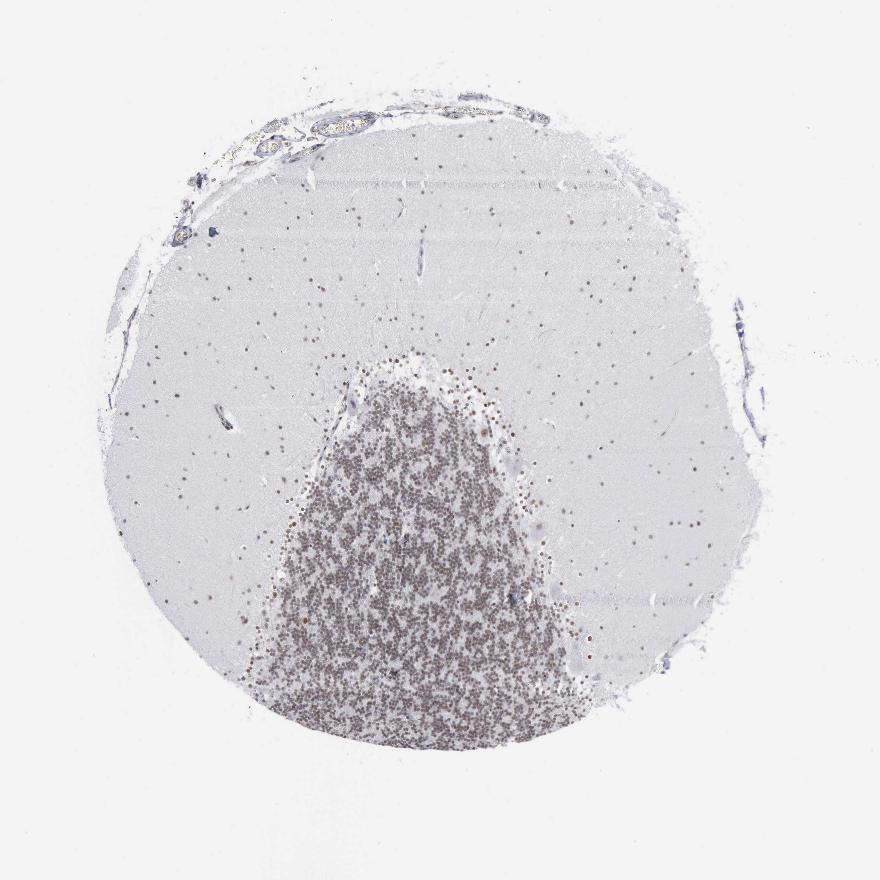

CEREBELLUM - Antibody stainingi

Antibody staining in the annotated cell types in the current human tissue is reported as not detected, low, medium, or high, based on conventional immunohistochemistry profiling in selected tissues. This score is based on the combination of the staining intensity and fraction of stained cells.

Each image is clickable and will lead to virtual microscopy that enables deeper exploration of all samples and also displays staining intensity scores, fraction scores and subcellular localization as well as patient and tissue information for each sample.

Antibody CAB000155

Purkinje cells Low

Cells in granular layer Low

Cells in molecular layer Low